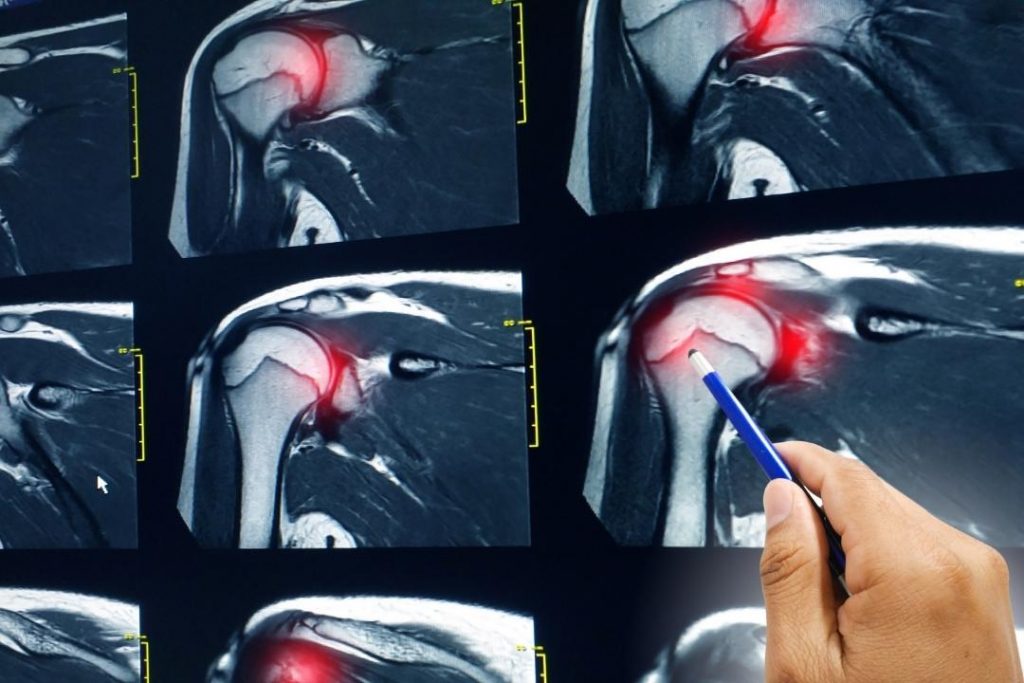

SLAP tears, on the other hand, are not always successfully exposed in ordinary labral tear shoulder MRIs and CTs. The use of arthrograms or arthrotomograms, like MR-arthrograms or CT-arthrograms, can help detect torn labrums to some extent. During an MR-arthrogram or CT-arthrogram (fluoroscopy), a dye will be injected into the shoulder to highlight the labral tear in shoulder.

Minor tears or even a complete lesion in the glenoid labrum may be missed by the radiologist. Such radiologist errors can lead to misdiagnosis and treatment delays.